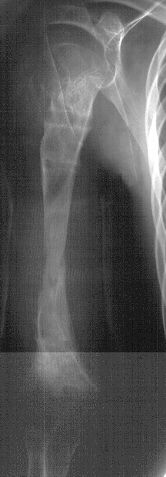

A three year one month old boy presented to AIDI with shortening of the right humerus. Clinical examination revealed 4 cm shortening of right arm and painless limitation of ROM of right shoulder; abduction was 150 degrees with 80 degrees at the glenohumeral joint and internal rotation was significantly limited. There was also 1 cm shortening of the right leg and a 10 degree valgus deformity of the same knee.

Radiological examination showed absence of proximal epiphysis of the right humerus with marked deformity of the metaphyseal region. There was mild shortening of the right tibia in association with destruction of the lateral part of the proximal metaphysis and epiphysis. The diagnosis was neonatal sepsis with multifocal osteomyelitis involving the right humerus and proximal right tibia.

Xrays at age 11 show significant angualtion developed in the humerus . However tibial growth was good .